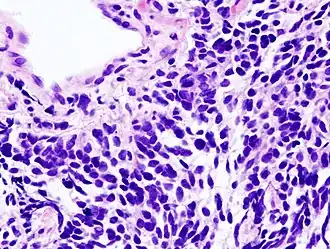

Longkanker wordt geclassificeerd naar histologisch type, dit is het oorspronkelijke celtype waaruit de kanker is ontstaan.[14] Deze classificatie is van belang voor bepaling van de behandeling en het voorspellen van het verloop van de ziekte. Verreweg de meeste vormen van longkanker zijn carcinomen, kwaadaardige tumoren die ontstaan vanuit epitheelcellen. Longcarcinomen worden ingedeeld naar de grootte en het uiterlijk van de kwaadaardige cellen zoals een histopatholoog die onder een microscoop ziet. Er wordt een globale tweedeling in niet-kleincellige en kleincellige longcarcinomen gebruikt.[36]

Kleincellig longkanker

Bij het kleincellige longkanker (SCLC) bevatten de cellen dichte neurosecretoire korrels (vesikels die neuro-endocriene hormonen bevatten), waardoor deze tumor gepaard gaat met een endocrien/paraneoplastisch syndroom (een reeks verschijnselen die wordt veroorzaakt doordat de kanker zelf hormonen afscheidt).[39] De meeste gevallen doen zich voor in de grote luchtwegen (primaire en secundaire bronchiën).[16] Deze kwaadaardige tumoren groeien snel en zorgen in een vroeg stadium van de ziekte voor uitzaaiingen. Zestig tot zeventig procent is al uitgezaaid wanneer de kanker merkbaar wordt. Dit type longkanker hangt sterk samen met roken.[2]